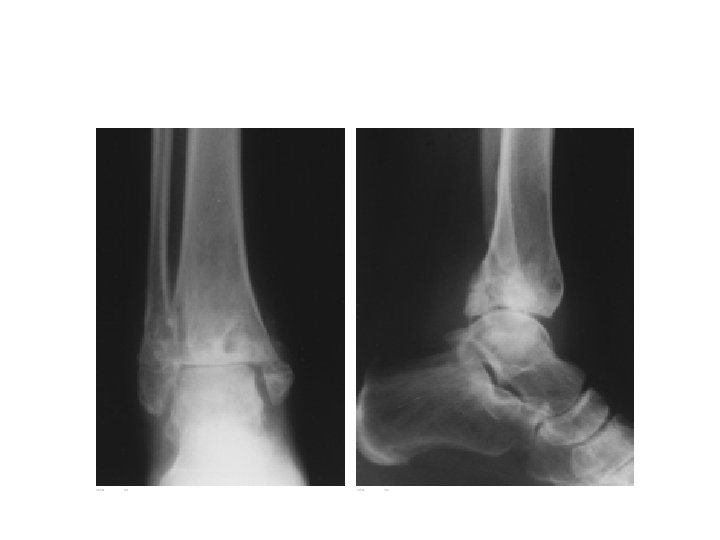

RADIOGRAPHIC EVALUATION • X RAY ANKLE (AP/LATERAL) INCLUDE AS MUCH OF DISTAL TIBIA • COMPUTED TOMOGRAPHY • NUCLEAR MEDICINE IMAGING